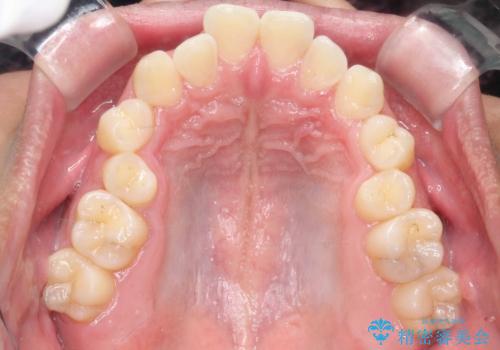

- 咬み合わせの不調和と歯並びのデコボコを主訴にご来院された患者様です。

精密矯正検査の結果、歯を抜かずに非抜歯でワイヤー矯正で治療を行う方針としました。

叢生(歯のデコボコ)の量が多く、加えてディープバイト(過蓋咬合)や重度の捻転も認められたため、リンガルアーチやマイクロインプラントなどの補助装置を併用し、治療を進めました。

治療途中では咬み合わせの改善を目的としてバイトアップを行い、歯の捻転や叢生を改善しつつ、機能的に安定した咬合を獲得しています。

治療期間は3年2ヵ月と比較的長期となりましたが、見た目の歯並びだけでなく、咬み合わせまでしっかり整えた症例です。

上顎左右4番は90度捻転していたため、改善後歯根露出してしまっているためCTG(歯肉移植)を行う予定です。